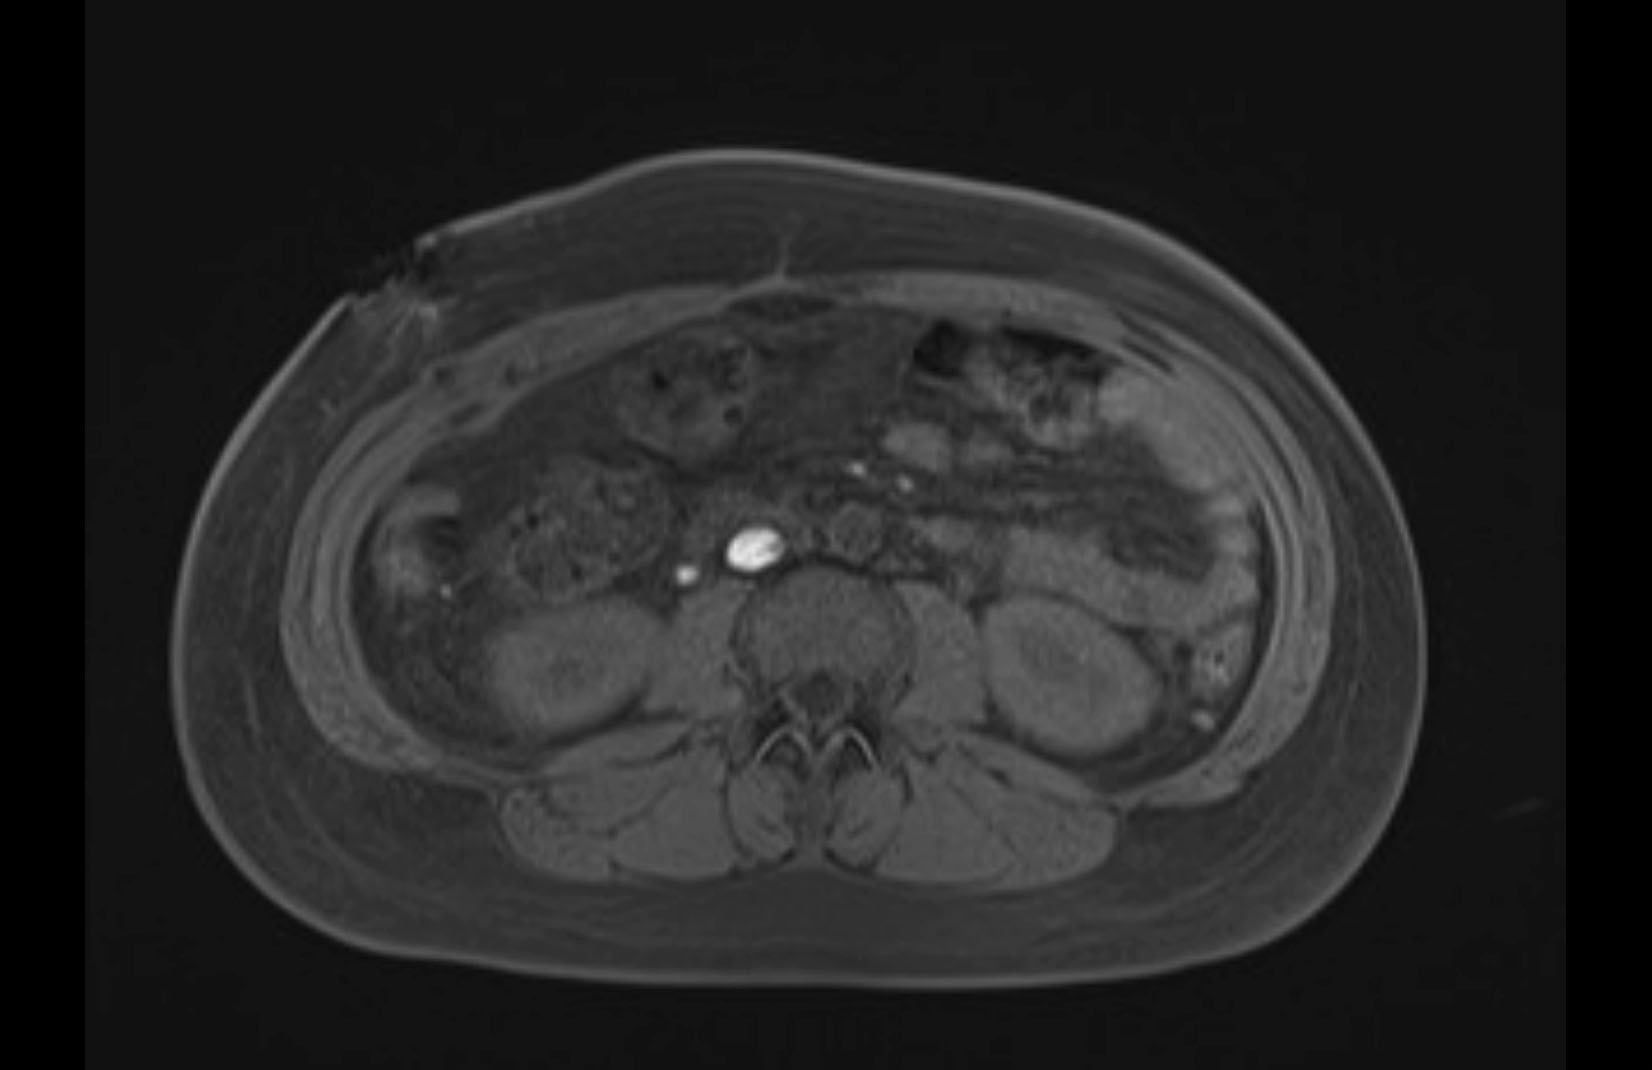

MRI T1

MRI T2